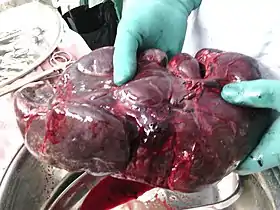

In humans, the spleen is purple in color and is in the left upper quadrant of the abdomen.[3][9] The surgical process to remove the spleen is known as a splenectomy.

Enlarged spleen

Enlargement of the spleen is known as splenomegaly. It may be caused by sickle cell anemia, sarcoidosis, malaria, bacterial endocarditis, leukemia, polycythemia vera, pernicious anemia, Gaucher's disease, leishmaniasis, Hodgkin's disease, Banti's disease, hereditary spherocytosis, cysts, glandular fever (including mononucleosis or 'Mono' caused by the Epstein–Barr virus and infection from cytomegalovirus), and tumours. Primary tumors of the spleen include hemangiomas and hemangiosarcomas. Marked splenomegaly may result in the spleen occupying a large portion of the left side of the abdomen.

Spleen Laparoscopic view of human spleen

Laparoscopic view of human spleen